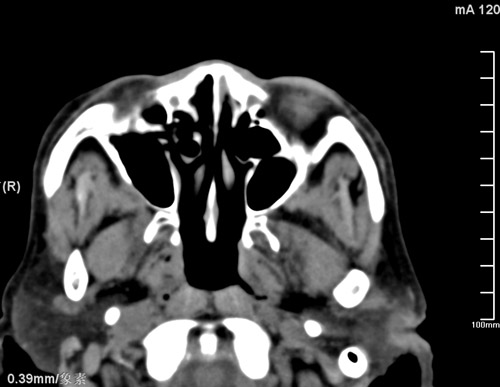

标题: CT17755:女,74 左鼻旁肿胀半年,临床以左上颌窦旁占位行CT [打印本页]

标题: CT17755:女,74 左鼻旁肿胀半年,临床以左上颌窦旁占位行CT

ct考虑鼻前庭囊肿 或鼻翼基底部慢性炎症,左上颌窦少许炎症 请指教

1)考虑左侧鼻前庭囊肿并感染。2)双侧上颌窦炎。

左侧鼻前庭囊肿并感染。双侧上颌窦炎。支持